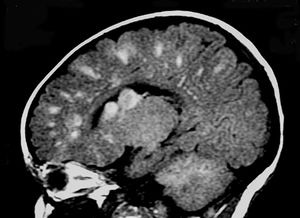

Image IQ Quiz: Young Patient Presents with Chronic SeizuresByM. Mohammed, M.D.March 30th 2021In a young patient with chronic seizures, what is the diagnosis?